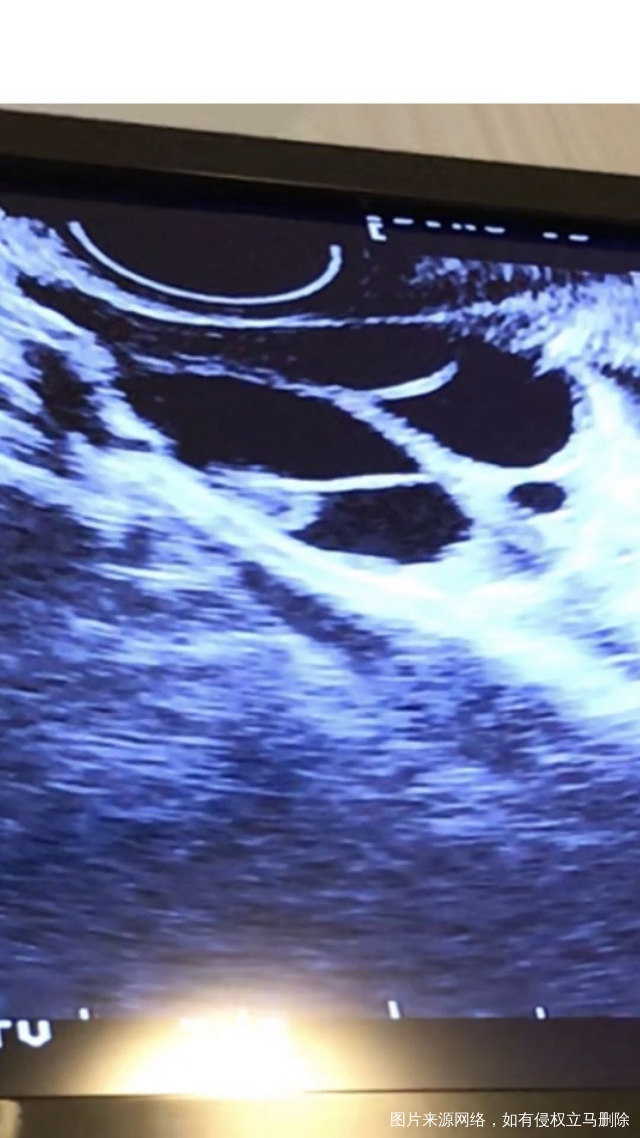

请医生帮我看一下b超图,这些是卵泡吗?大概有几个卵泡?卵泡很大吗?